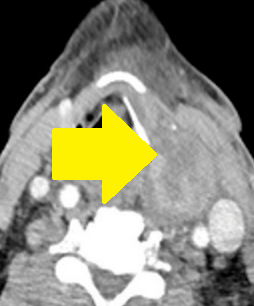

Contrast-enhanced CT demonstrates soft-tissue lesion in left carotid sheath (Courtesy Dr. V. Penopoulos)